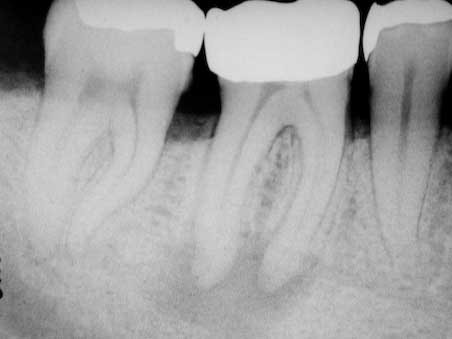

Apikale Aufhellung Zahn 46

Veröffentlicht 16. Februar 2009 am 452 × 339 in Apikale Aufhellung (3)